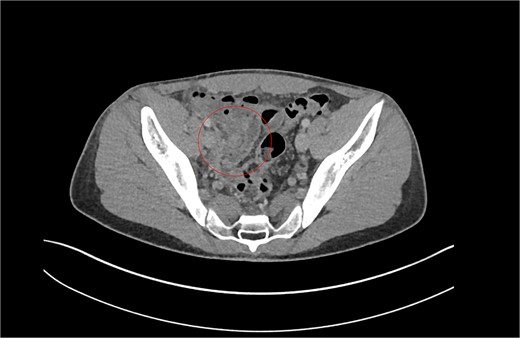

Patient A. Appendiceal stump of Patient A identified within the red circle on CT scan before the second operation.

Review of previous notes revealed that the patient had a laparoscopic appendicectomy 2 years prior from a CT-confirmed acute retrocaecal appendicitis with localized perforation at the tip (Fig. 1). Intraoperatively, the dissection proved difficult due to the presence on multiple inflammatory adhesions and the retrocaecal position of the appendix, however a retrograde appendicectomy was completed laparoscopically. The postoperative period was complicated by a right iliac fossa abscess that was successfully treated with IV antibiotics and CT-guided drainage. The index histology revealed multiple pieces of appendiceal tissue aggregating to 60 mm × 40 mm × 20 mm, with acute inflammation and necrosis.

Having had a previous appendicectomy with for perforated acute appendicitis with a postoperative collection, the differential diagnoses raised on CT KUB were either a stump appendicitis or a terminal ileitis. The patient was commenced on IV co-amoxiclav and formal contrast enhanced computer tomography of the chest, abdomen, and pelvis (CT CAP) was organized, revealing a residual long appendiceal stump infection associated with a small localized collection and caecal thickening.